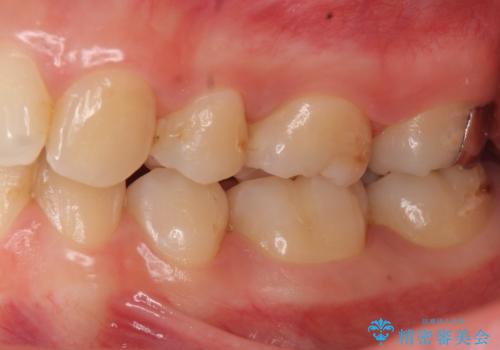

歯と歯の間の虫歯治療 セラミックインレーで治療

- 奥歯の歯と歯の間が虫歯になっていました。

セラミックインレーで治療しました。

- 14万円 左下56:セラミックインレー7万円×2本費用は治療当時の料金となります